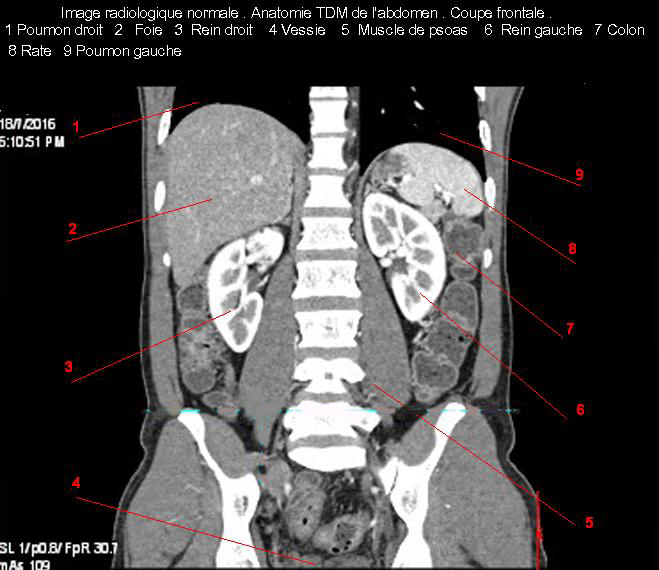

Images radiologique normale de abdomen en coupe frontale ( Coronale )  :